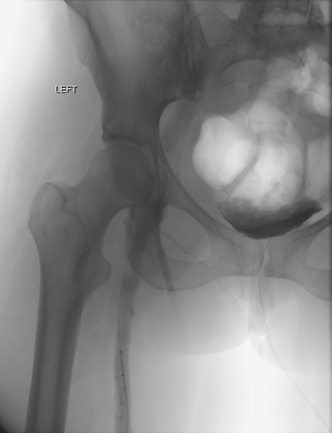

Venograma en posición de decúbito prono de la rama ilíaca izquierda que indica una estenosis causada por el tumor que comprime la uretra y la vena ilíaca externa izquierda.